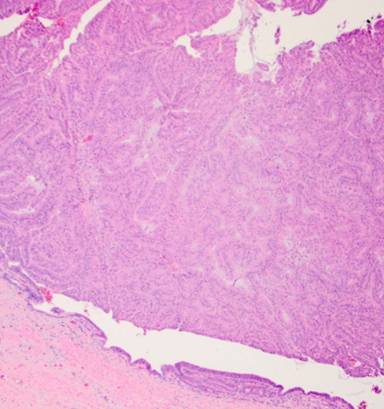

Secondary to her disease being potentially resectable, a diagnostic laparoscopy was performed to rule out extrahepatic disease. Biopsy of the segment 6 liver lesion demonstrated infiltrating glands staining diffusely for CK7, CK19, and CK20 consistent with a gallbladder primary (Figures 3 and 4). Concern was raised about the size of the left hemi-liver and the patient underwent portal vein embolization.

Figure 3. Histology of original gallbladder primary demonstrating well-to-moderately differentiated papillary gallbladder adenocarcinoma with invasion into lamina propria. |

The pathology specimen demonstrated a 10.0x6.5x0.5 cm papillary, pink, circumferential tumor located primarily in the body and neck of the gallbladder. Additional papillary areas that were non-contiguous with the main tumor were also identified in the body and fundus. The final cystic duct and liver margins were negative for any evidence of malignancy. Adenocarcinoma present in the liver resection specimen was morphologically identical to the gallbladder primary tumor (Figures 5 and 6). There was evidence of lympho-vascular invasion; however, no lymph nodes were identified in the sizable portal node dissection specimen. The patient underwent adjuvant chemotherapy with cisplatin and gemcitabine for six months and was followed by her local medical oncologist with tumor markers and serial imaging. Two years after her initial diagnosis, PET-CT showed a new 25x17 mm hypodense mass in the pancreatic head involving the main pancreatic duct causing mild upstream duct dilation and pancreatic parenchymal atrophy (Figure 7). There was no evidence of vascular invasion or biliary dilation on CT imaging. Endoscopic ultrasound showed a round hypoechoic mass in the inferior aspect of the pancreatic head and uncinate process measuring 23x21 mm in maximal cross section diameter. A fine needle aspirate (FNA) of the pancreas head mass demonstrated metastatic gallbladder carcinoma consistent with patient’s gallbladder primary.

Figure 5. Histology of metastatic papillary adenocarcinoma to the liver identical to gallbladder primary. |